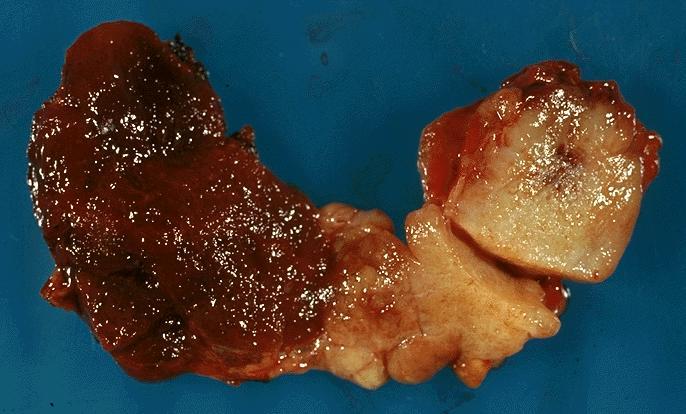

Gross description

- Sporadic: typically presents as a single circumscribed but nonencapsulated, gray-tan mass

- Familial: generally bilateral / multiple foci

- Solid, gray-tan-yellow, firm, may be infiltrative

- Larger lesions have hemorrhage and necrosis, tumor usually in mid or upper portion of gland (with higher density of C cells)

- < 1 cm in size is called microcarcinoma; if < 0.5 cm, associated with a complete absence of clinically detectable metastatic disease (Ann Surg Oncol 2009;16:2875)

Gross images

Contributed by Mark R. Wick, M.D.

AFIP images